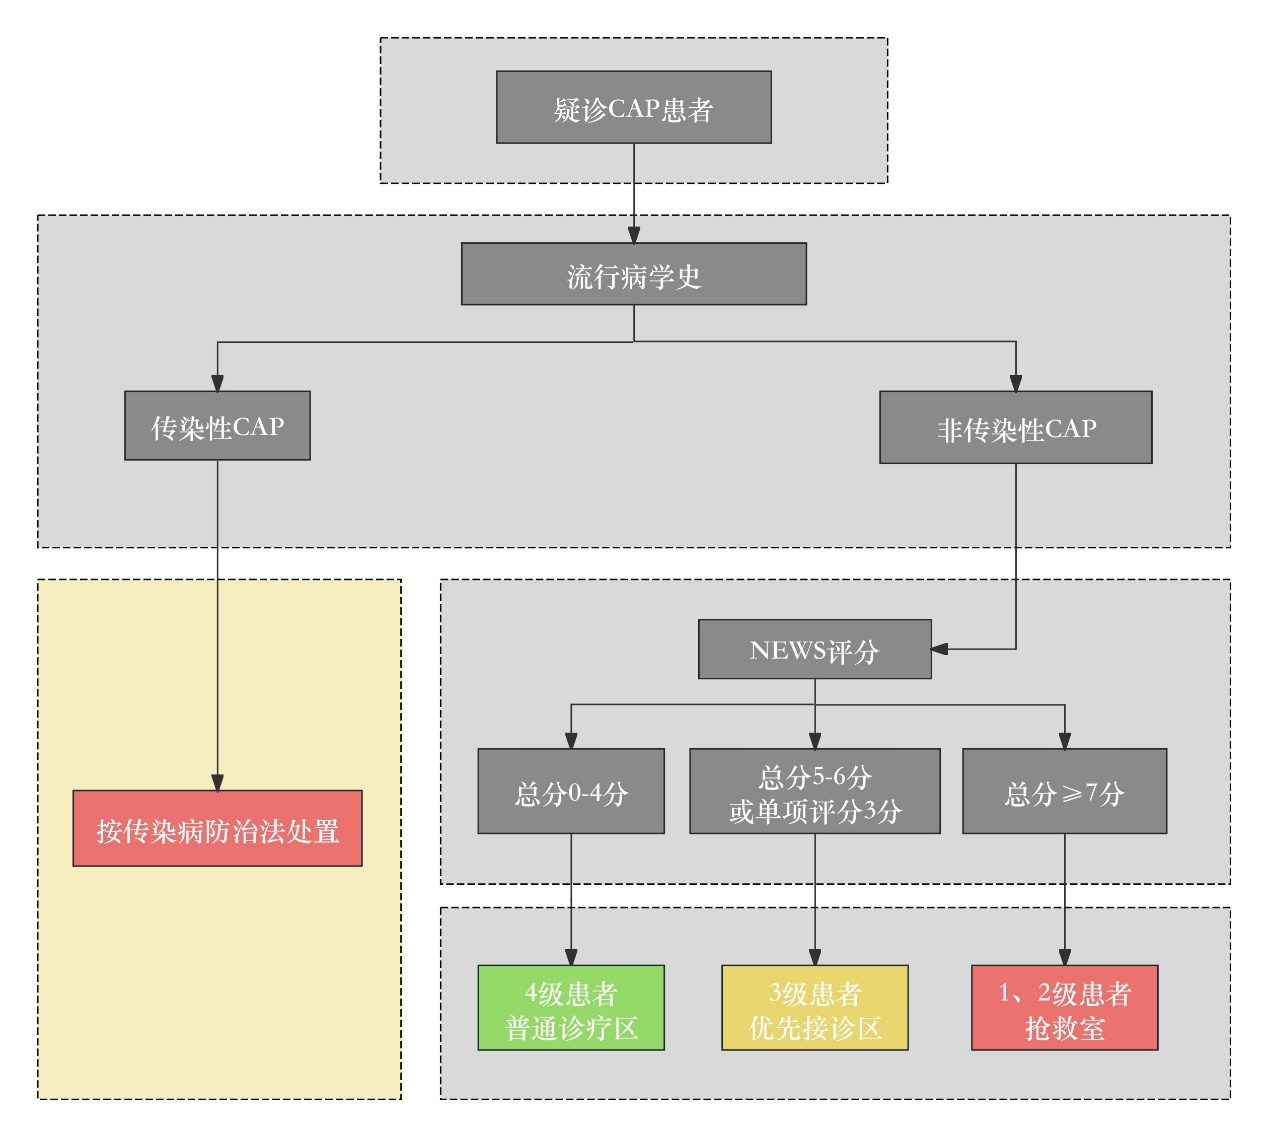

患者至急诊分诊台后,分诊护士应快速评估。若患者有发热、咳嗽、咳痰或原有呼吸道疾病症状加重,可疑诊为CAP。结合患者的流行病学史,若考虑传染性CAP则按传染病防治法处置;对于非传染性CAP,通过NEWS评分进行危险分层并决定诊疗地点(图 1)。

| 图 1 社区获得性肺炎急诊预检分诊流程 |

推荐意见2:对疑诊CAP的急诊患者推荐使用NEWS评分按流程进行预检分诊,以决定患者的就诊场所(证据等级Ⅱ,推荐等级B)。